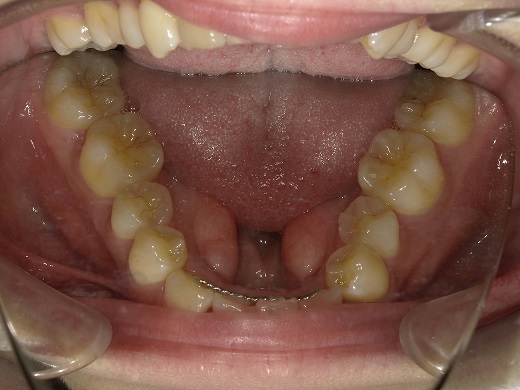

治療後下顎